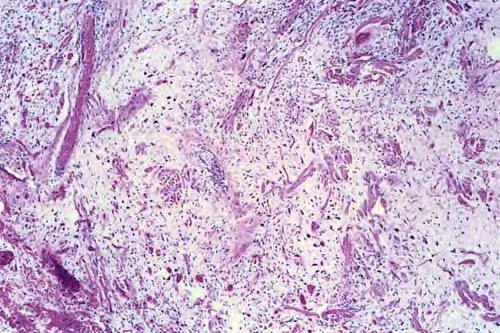

Pleomorphic lipoma = الشحموم متعدد الاشكال